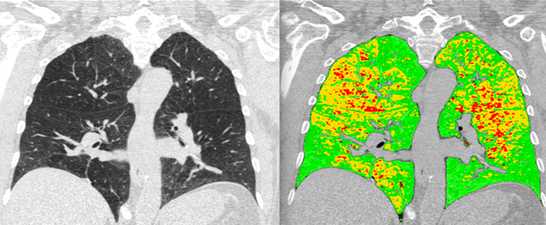

- Functional imaging of large and small airways

- Imaging of COPD and smoking-related disease

- Imaging of fibrosing lung disease